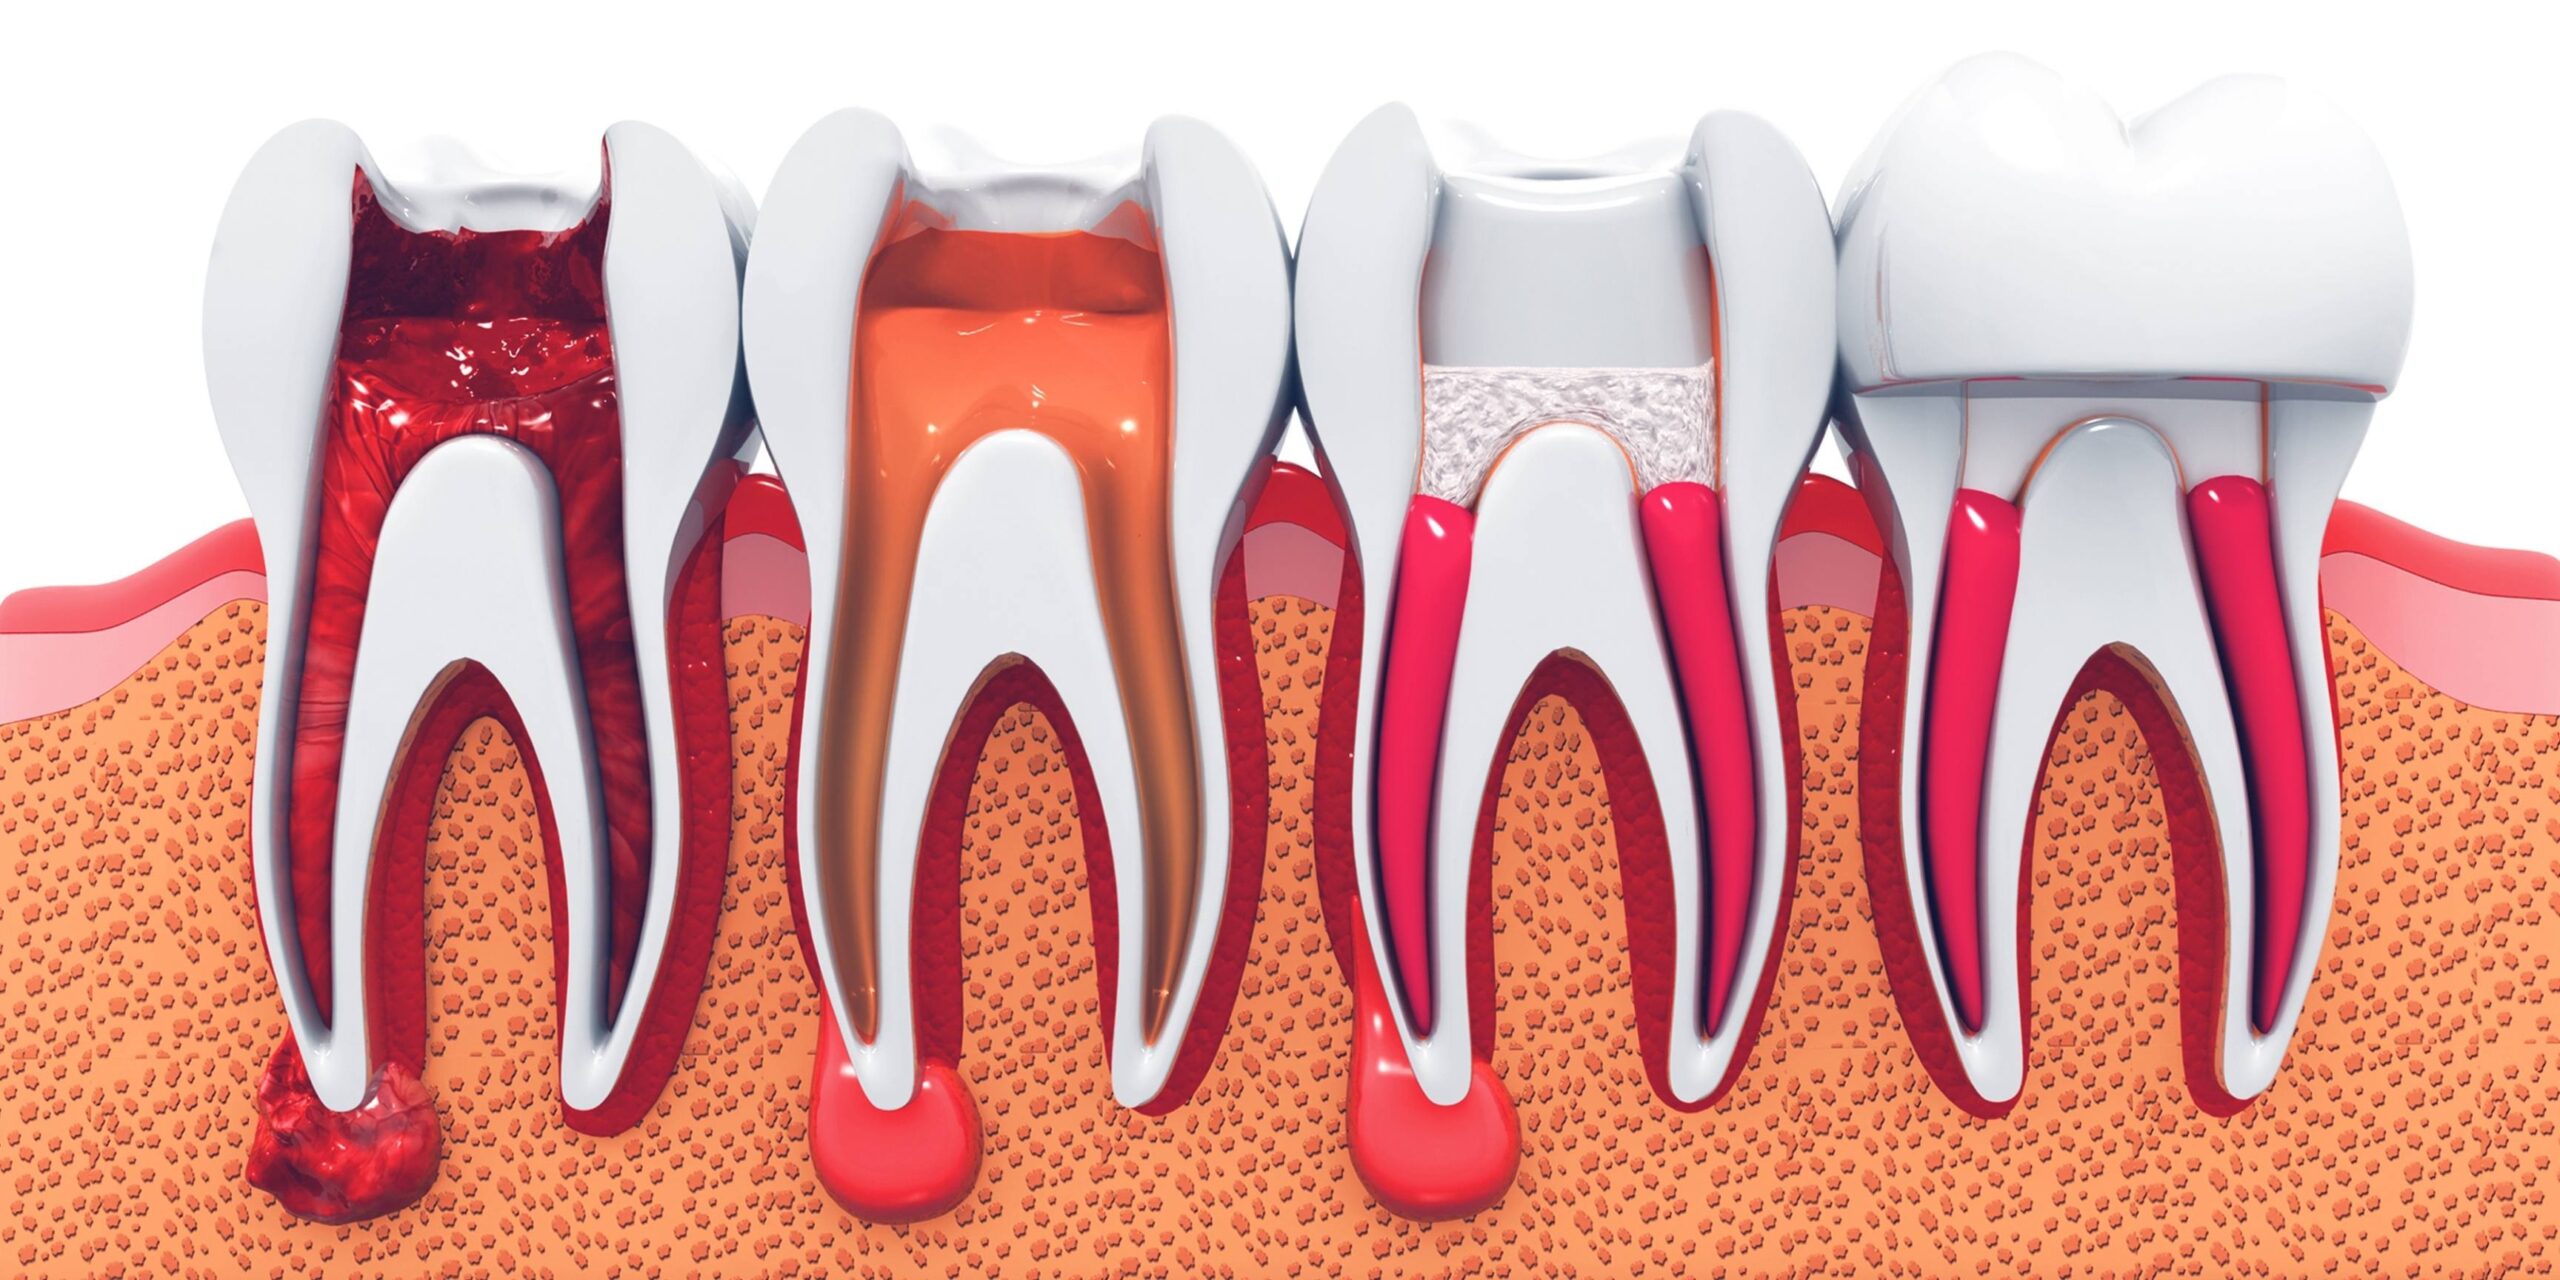

O tratamento de canal tem se tornado um procedimento mais simples e confortável com o avanço das técnicas e da tecnologia. Normalmente, o tratamento de canal é recomendado quando há infecção na polpa do dente. Então, de uma forma resumida, o tratamento de canal consiste no dentista tratar o tecido da polpa do dente, infeccionado por alguma bactéria. Muitas vezes essa infecção por bactérias é causada por cáries não tratadas, infiltrações por má adaptação de restaurações ou até mesmo pós-traumas.